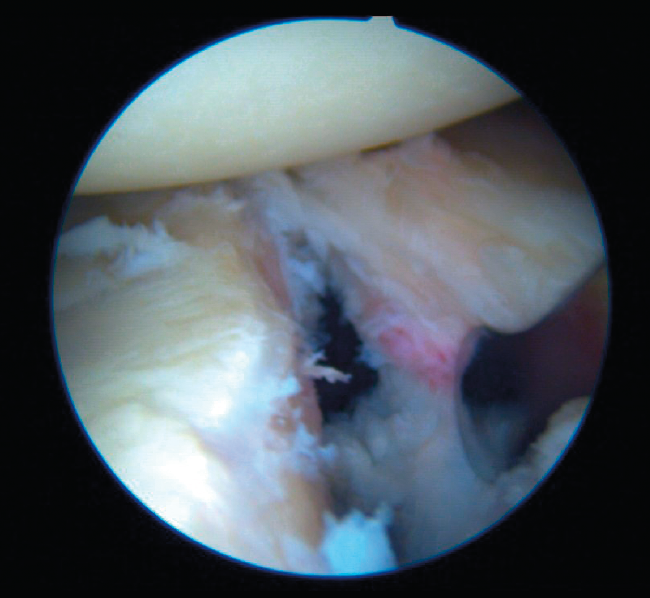

Once the Bankart lesion has been confirmed, we detach and mobilize the capsulolabral complex from the glenoid neck with arthroscopic rasps and/or dissectors until satisfactory and subscapular fibers are visualized (Figure 7). Before implant placement, it is necessary to perform decortication of the anterior glenoid neck using a 4-mm synoviotome. Repair is started after this step, always working from lower to upper.

Figure 7. Detachment and mobilization of the labrum.